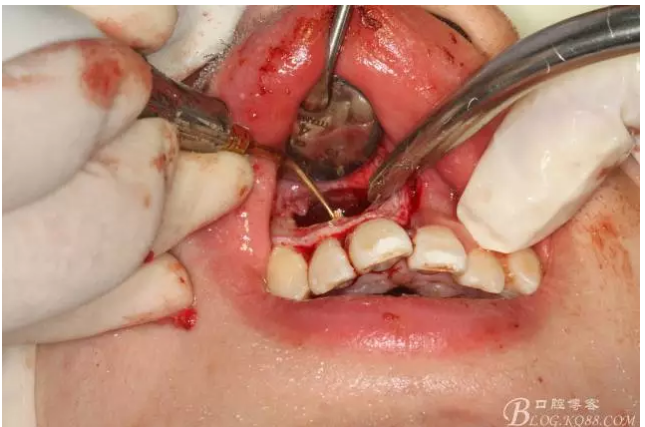

圖2.根管治療術(shù)后直接局部 麻醉下切開、翻瓣,發(fā)現(xiàn)12唇側(cè)骨壁有綠豆大小骨缺損

圖3.依缺損部位為中心,逐漸去骨,完整暴露出囊壁。